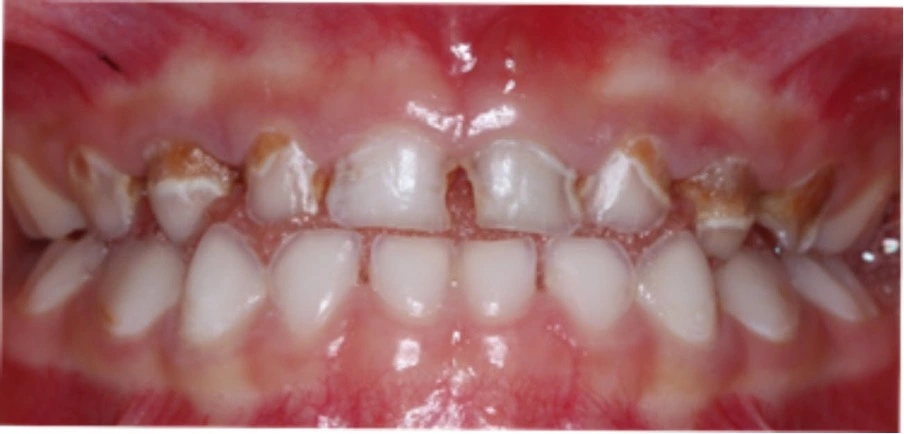

Lalloo menyimpulkan bahwa anak hiperaktif dua kali lebih mungkin mengalami cedera pada wajah dan/atau gigi dibandingkan dengan kelompok kontrol berdasarkan data dari Survei Kesehatan Inggris tahun 1997. Hal ini dapat dikaitkan dengan keterlibatan mereka dalam kekerasan akibat gangguan perilaku. Mereka memiliki indeks plak yang tinggi dan aliran saliva yang rendah, sehingga menyebabkan gigi cepat mengalami karies (berlubang). Menggigit kuku dan bruksism adalah kebiasaan umum yang terlihat. Mereka juga lebih mungkin menderita kekerasan fisik dari orang tua yang belum memahami ADHD daripada dari anak pada umumnya.

- Karies gigi: Kebiasaan makan tidak teratur, konsumsi makanan manis/snacking, kurangnya rutinitas kebersihan mulut, dan pengawasan oral yang kurang sehingga meningkatkan risiko karies (gigi berlubang).

- Plak dan gingivitis: Sikat gigi yang tidak efektif dan frekuensi pembersihan yang rendah menyebabkan akumulasi plak dan peradangan gusi.